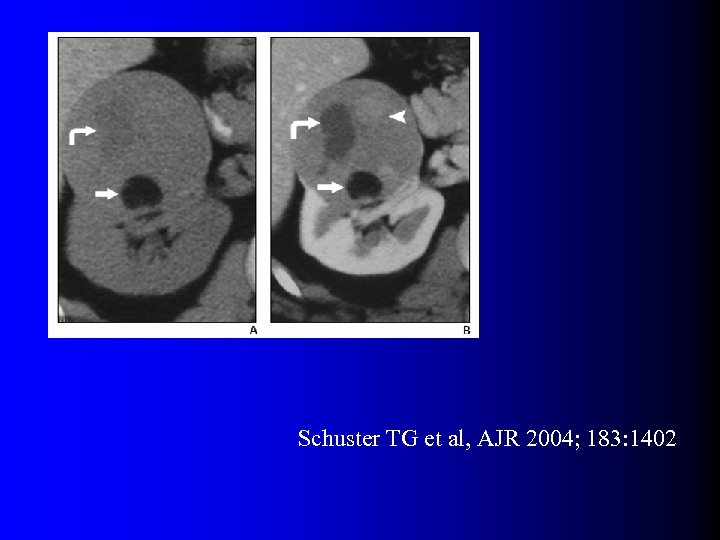

Tumeurs malignes à contenu graisseux l OUI… presque l Quelques rares exceptions dans la littérature – Incorporation de graisse péri-rénale ou sinusale dans une volumineuse tumeur – Métaplasie osseuse avec éléments graisseux de moelle osseuse – Nécrose cholestérolique intra-tumorale (1) Hélénon O et al, Radiographics 1997; 17: 129 (2) Henderson RJ et al, J Urol 1997; 157: 1347 (3) Roy C et al, Br J Urol 1998; 71: 977 (4) Schuster TG et al, AJR 2004; 183: 1402

Tumeurs malignes à contenu graisseux l OUI… presque l Quelques rares exceptions dans la littérature – Incorporation de graisse péri-rénale ou sinusale dans une volumineuse tumeur – Métaplasie osseuse avec éléments graisseux de moelle osseuse – Nécrose cholestérolique intra-tumorale (1) Hélénon O et al, Radiographics 1997; 17: 129 (2) Henderson RJ et al, J Urol 1997; 157: 1347 (3) Roy C et al, Br J Urol 1998; 71: 977 (4) Schuster TG et al, AJR 2004; 183: 1402

Tumeurs malignes à contenu graisseux l Eléments diagnostiques: – Calcifications +++ – Large nécrose intra-tumorale avec petits foyers graisseux – Association avec ADP et thrombus tumoral non graisseux l D'une manière générale, se méfier d'un "AML" à croissance rapide…

Tumeurs malignes à contenu graisseux l Eléments diagnostiques: – Calcifications +++ – Large nécrose intra-tumorale avec petits foyers graisseux – Association avec ADP et thrombus tumoral non graisseux l D'une manière générale, se méfier d'un "AML" à croissance rapide…

Schuster TG et al, AJR 2004; 183: 1402

Schuster TG et al, AJR 2004; 183: 1402